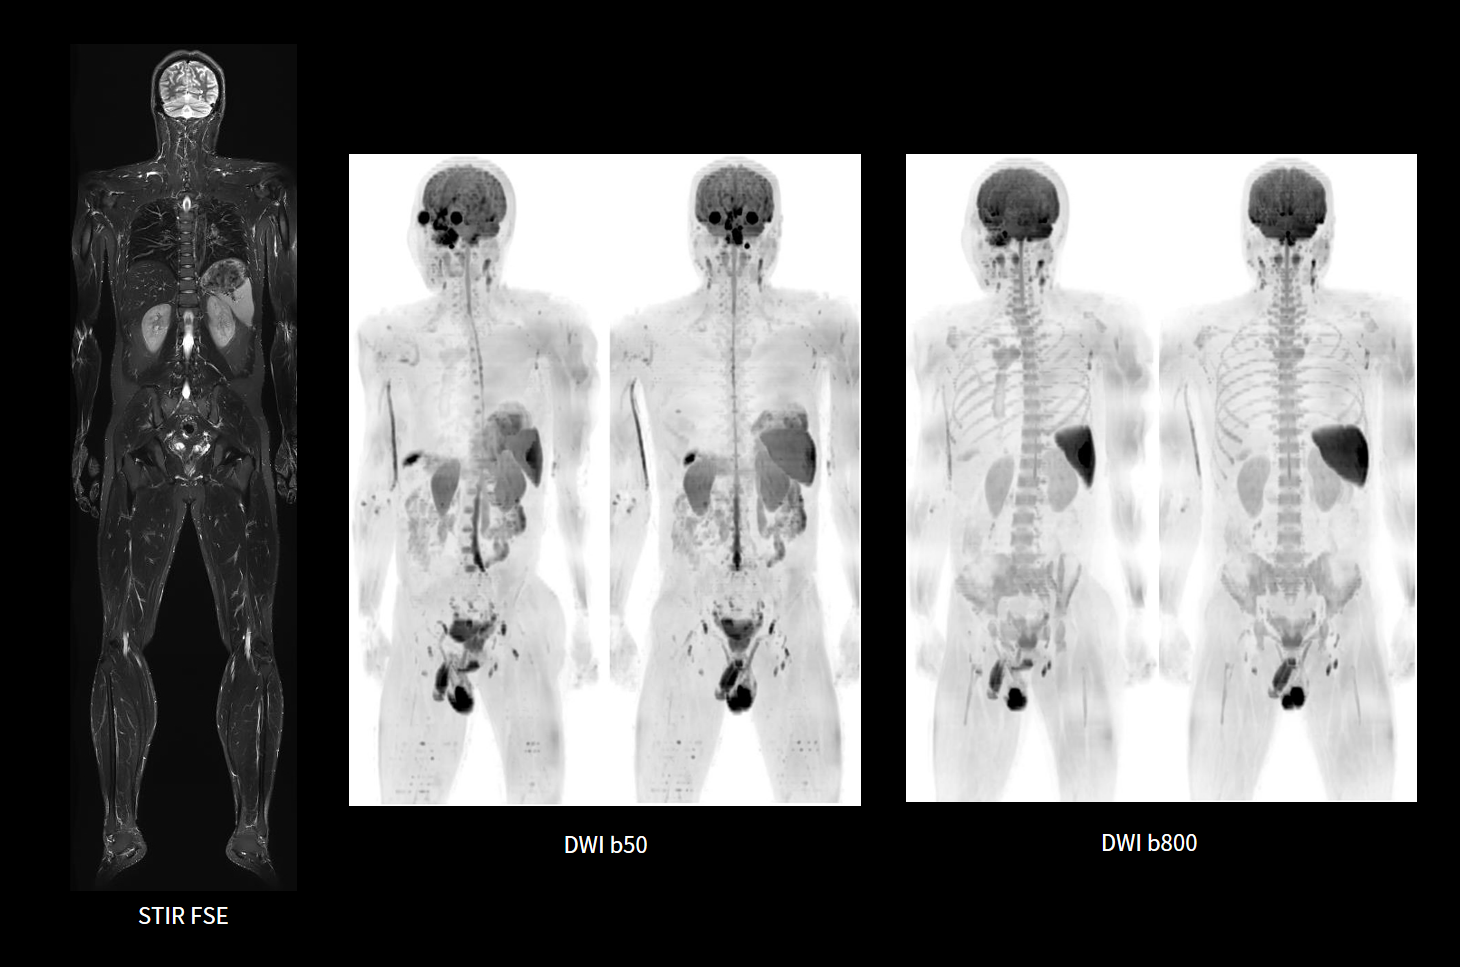

DWI whole-body

Câmp vizual larg

Ideal pentru scanări multi-pat, precum imagistica întregii coloane vertebrale sau a întregului corp.